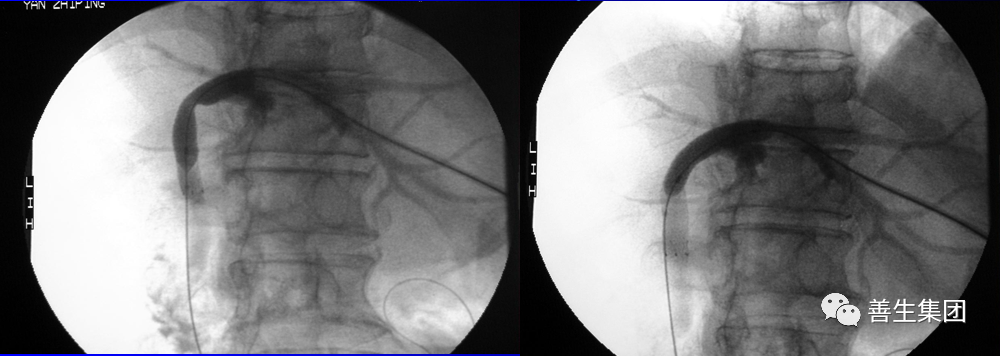

PTC示左右肝管内间广泛充盈缺损,为胆道出血正像

胆管支架什么样子经皮肝胆管穿刺置管引流术(PTCD)及胆道内支架临床应用_https://www.jmylbn.com_新闻资讯_第5张